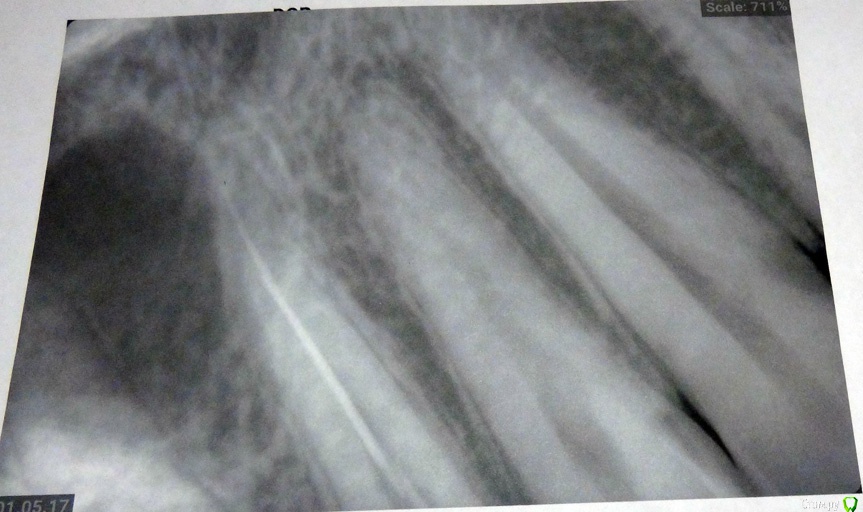

Ниже прилагаю два снимка один - это вроде бы снимок   перед пломбировкой каналов с инструменами.

Второй  -это после пломбировки каналов + временная пломба.

Нормально ли каналы запломбировали?